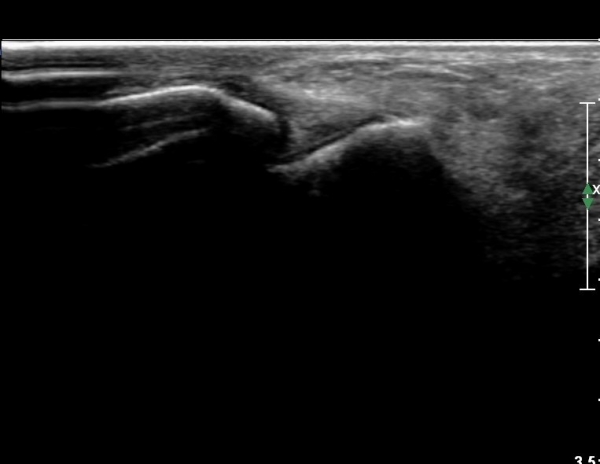

Àü°ÅºñÀδë Á¾´Ü¸é°Ë»ç¿¡¼­  Àü°ÅºñÀδëÀÇ ÆÄ¿­À» º¸ÀÓ(»çÁø 2).